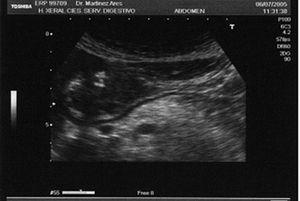

Se trata de una paciente de 50 años de edad, intervenida de un adenocarcinoma de endometrio en estadio T3 N1 M0 en 1996 y tratada con radioterapia externa adyuvante, sin otros antecendentes personales de interés. Refería epigastralgia de 6 meses de evolución que trató intermitentemente con omeprazol. En una tomografía computarizada (TC) abdominopélvica realizada como revisión rutinaria por su cáncer de endometrio, se puso de manifiesto una masa heterogénea de 4 cm en el antro gástrico. Por este motivo, se indicó una gastroscopia, que confirmó la presencia de una tumoración submucosa antral ulcerada de unos 4 cm, redondeada y de consistencia firme. Se realizó a continuación una ecografía hidrogástrica, visualizándose la lesión bien delimitada con un tamaño de 44 * 28 mm, de bordes regulares, ecogenicidad ligeramente heterogénea, con algún espacio quístico en su interior, con dos úlceras en superficie, una muy superficial y otra de al menos 1 cm de profundidad. El tumor era dependiente de las primeras 3 capas, y mostraba una capa muscular propia totalmente preservada (fig. 1). Con el diagnóstico de un tumor submucoso probablemente maligno se indicó tratamiento quirúrgico. Se realizó una antrectomia que incluía el tumor, la vagotomía y la anastomosis gastroduodenal. En la pieza quirúrgica se observó una lesión de 50 * 25 mm, de coloración blanquecina, ovoidea, de consistencia firme y con dos úlceras en la superficie (fig. 2). El estudio histológico reveló un tumor bien delimitado aunque sin cápsula, con células de aspecto epiteliode que presentaban un moderado pleomorfismo nuclear; en el estudio inmunohistoquímico se observó que las células neoplásicas expresaban CD 117, CD 34 y vimentina (fig. 3). También se expresaba p53 y el índice MIB-1 era del 3%. El tumor respetaba integramente la capa muscular propia. El diagnóstico definitivo fue de tumor estromal gastrointestinal (GIST) de riesgo intermedio y, dado que se consideró que la resección había sido completa, inicialmente no fueron contempladas otras terapéuticas adicionales.

Fig. 1. La ecografía hidrogástrica revela una lesión bien delimitada, dependiente de las primeras 3 capas, con una capa muscular propia (cuarta capa hipoecogénica) completamente respetada en toda su extensión. El tumor presenta un patrón ultrasonográfico sugestivo de malignidad, mide unos 45 mm de diámetro mayor, y presenta una gran ulceración en la superficie (punta de flecha).